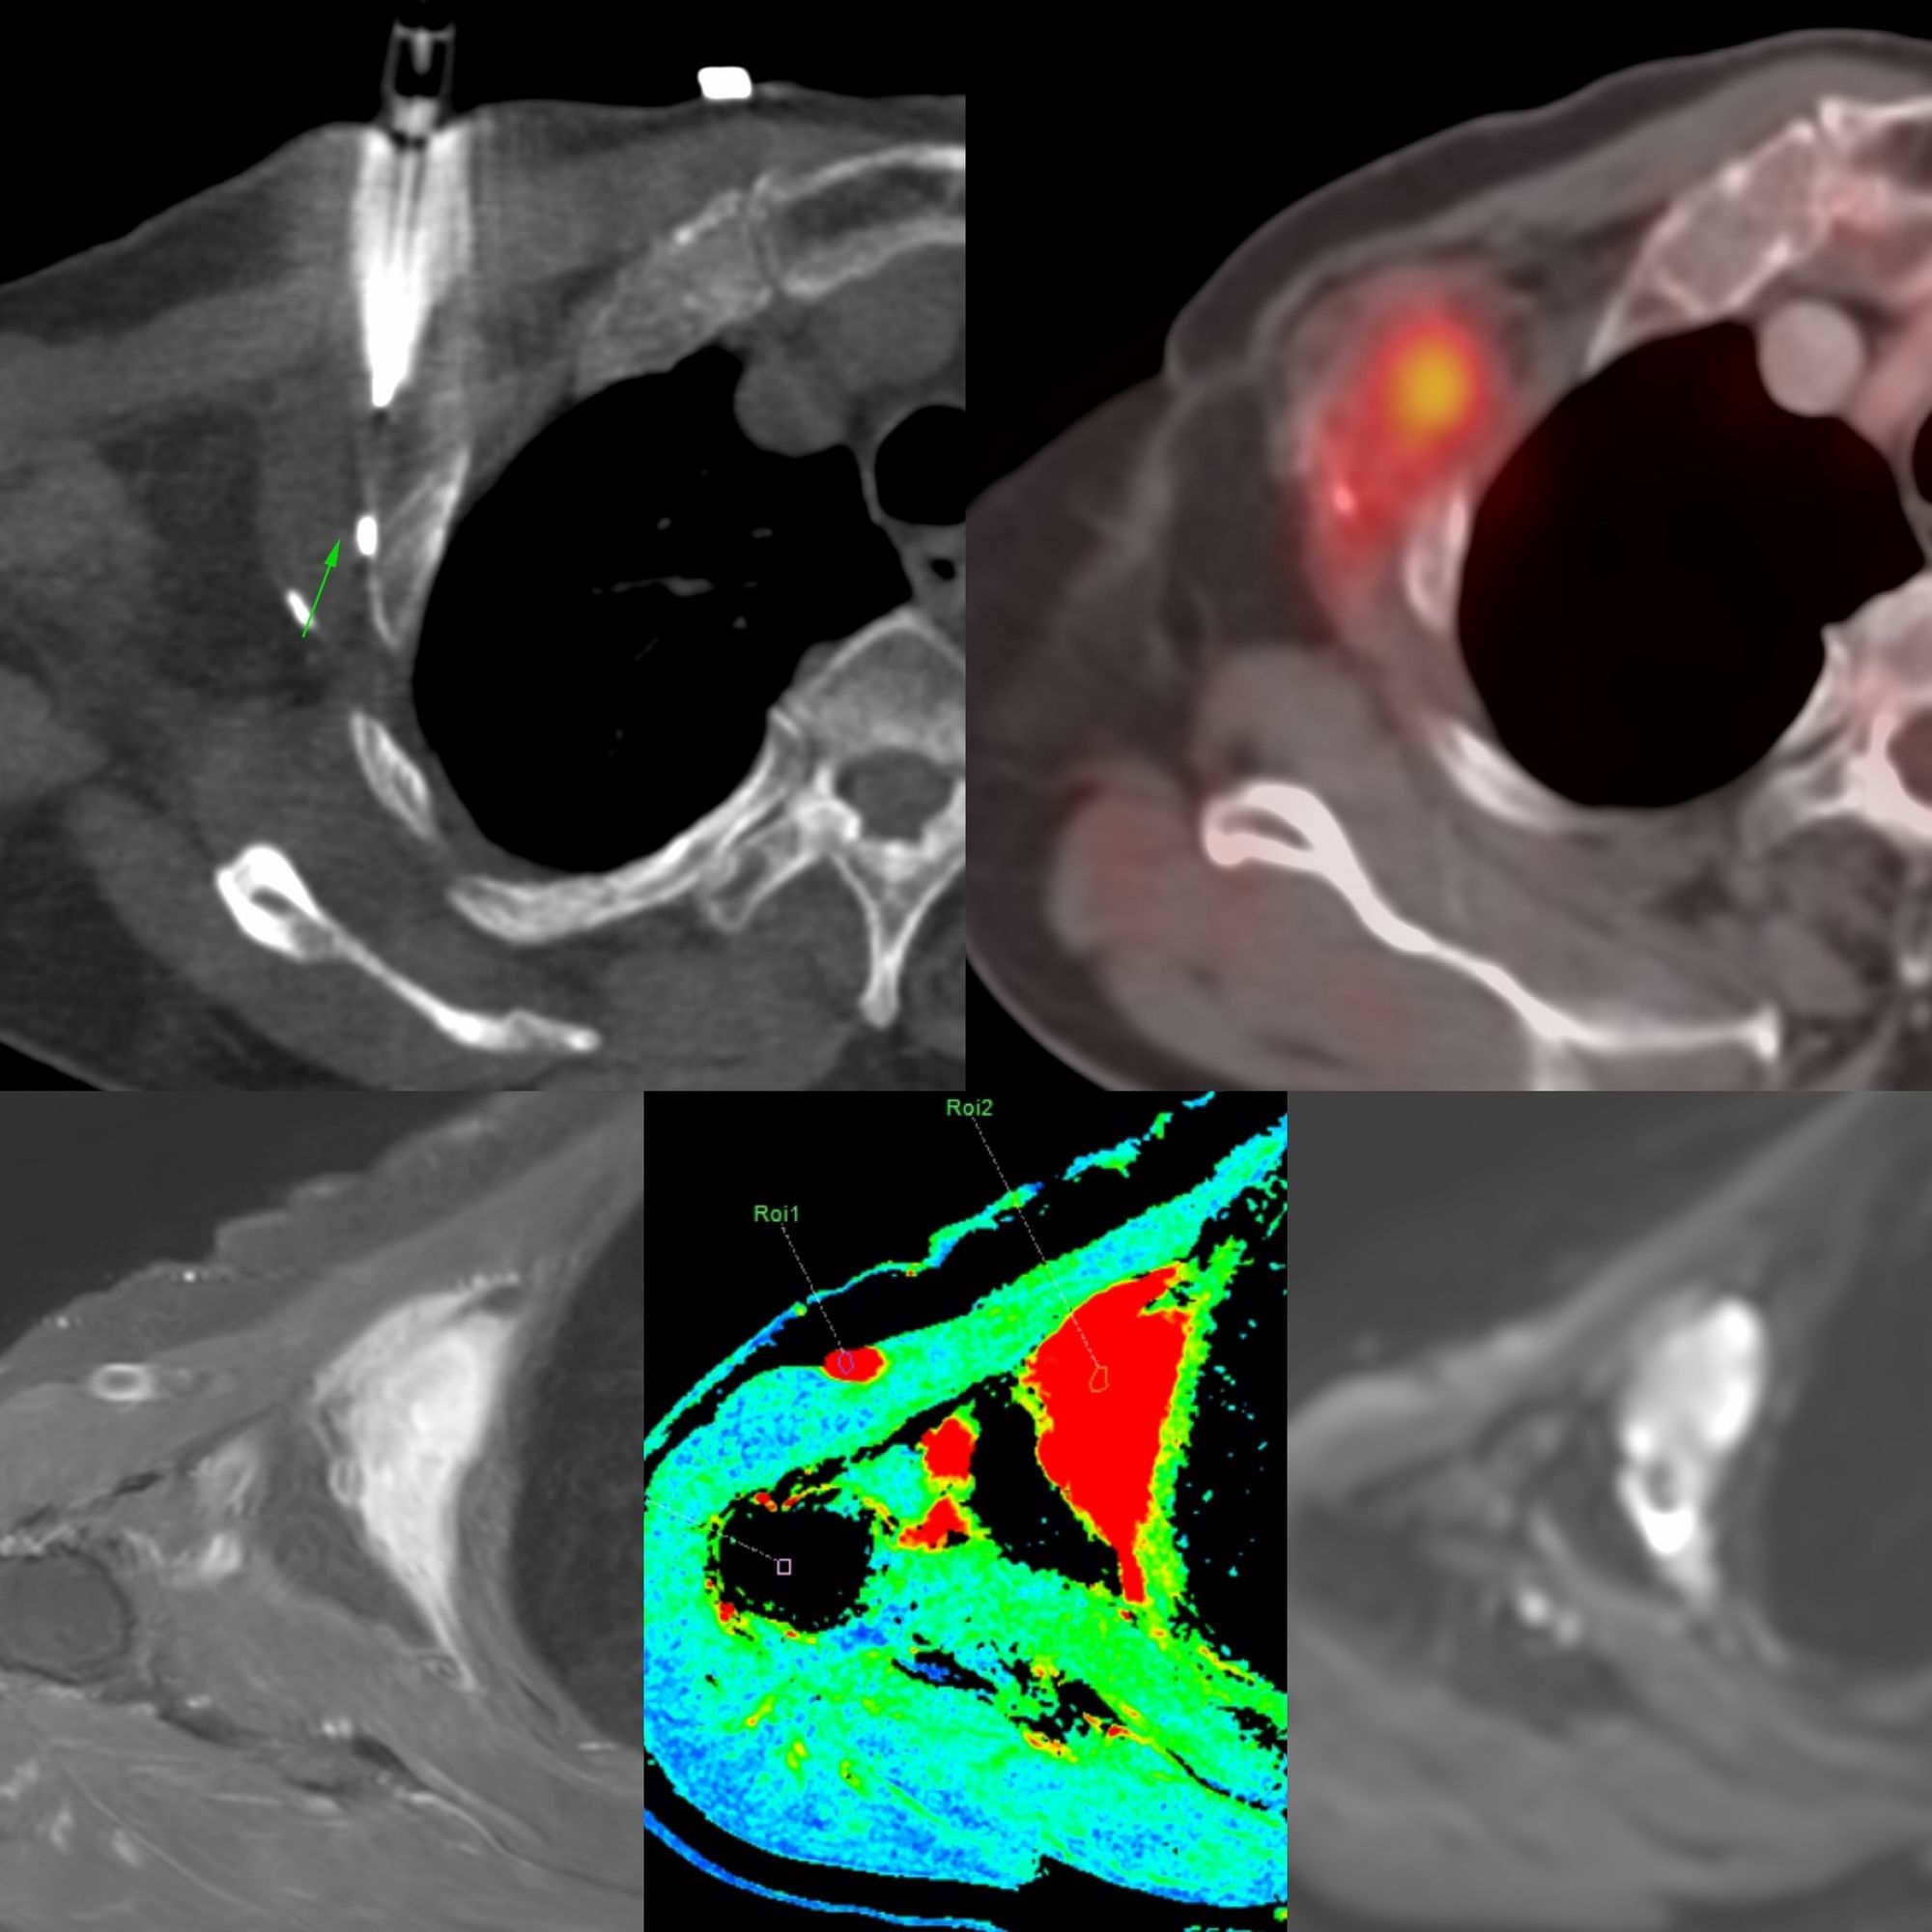

Case 28: Adipocytic Tumor Thigh - High Grade Liposarcoma

Bhavin Jankharia - 30 April 2021